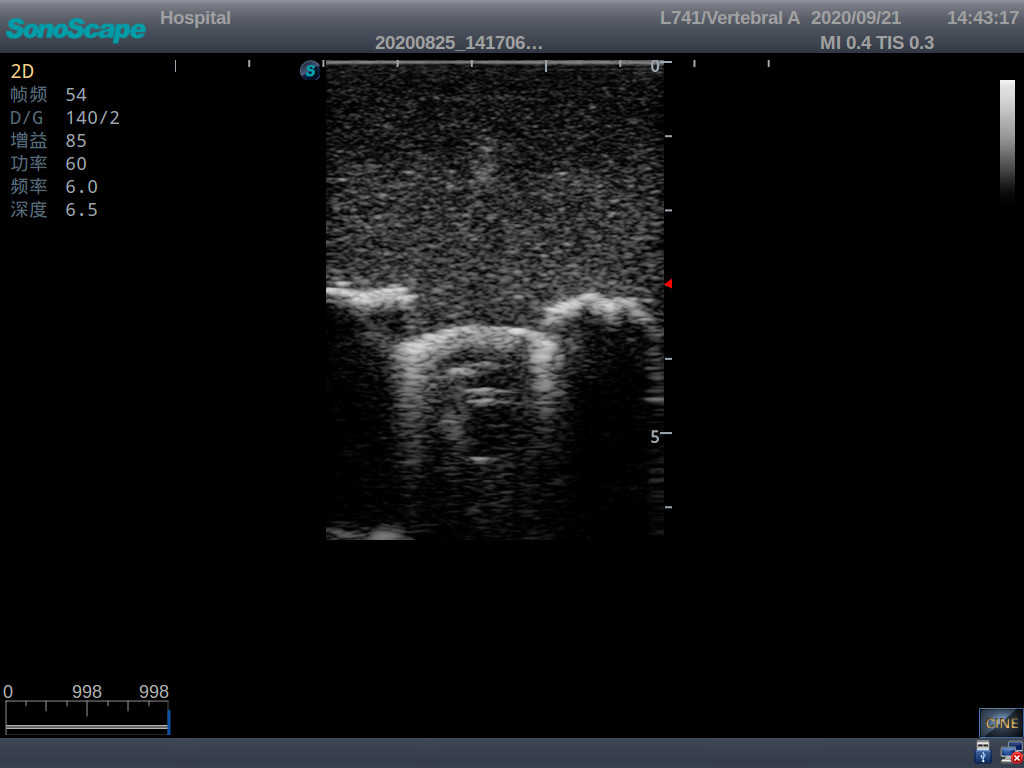

Pediatric Lumbar Puncture Ultrasound Training Model

Model TYE1558.1

This model is an ideal choice for ultrasound-guided pediatric lumbar puncture training with true-to-life skin feel and touch, accurate anatomical structures as well as real clinical ultrasound images. Realistic resistance to needle tips and correct landmarks provide excellent hands-on experience.

Accurate anatomical structure of L1-L5 and the vertebral canal

2)  Real clinical ultrasound images

3)  Compatible with various real ultrasound machines